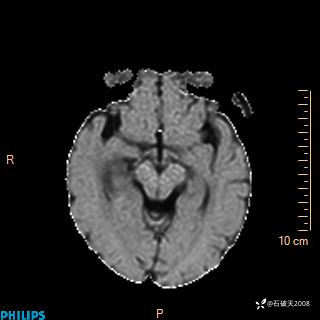

颅内占位,影像征象不是很丰富,有病理

hyy838 推荐女 62岁 主 诉:头晕12小时,加重1小时。

现病史:患者于12小时前无明显诱因出现头晕,呈持续性,无天旋地转及行走不稳,伴恶心、呕吐,呕吐共5次,呕吐物为胃内容物(具体性质不详),无胸闷、胸痛、心慌,无腹痛、腹泻,无咳嗽、咳痰,无发热、意识不清、肢体抽搐及大小便失禁等,1小时前患者上述症状加重,未诊疗,为求进一步治疗急自行来我院,门诊以“头晕待查”为诊断收入我科,发病来,神志清,精神差,饮食、睡眠差,大小便正常,体重未见明显下降。

FILAR